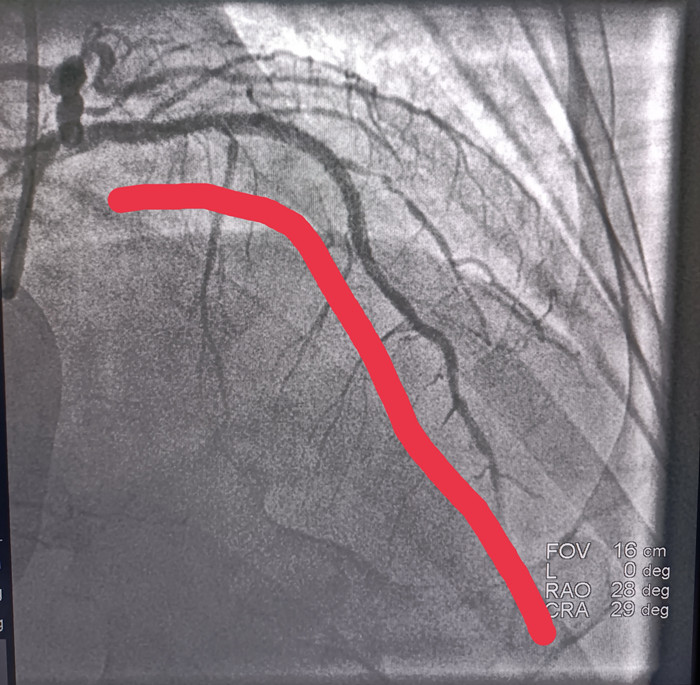

在患者被推到导管室门口 , 患者心脏再次室颤 , 医生再次电击除颤;这时候导管室早在20分钟前做好了一切手术准备 。 患者造影很顺利 , 造影显示心脏做大血根部堵塞 , 经过导丝通过 , 球囊扩张 , 血流显影 , 支架植入 , 血流恢复 。

手术前